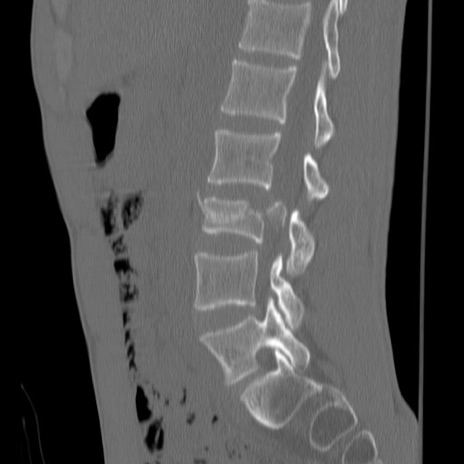

症例3 腰椎CT(矢状断像)

腰椎CT